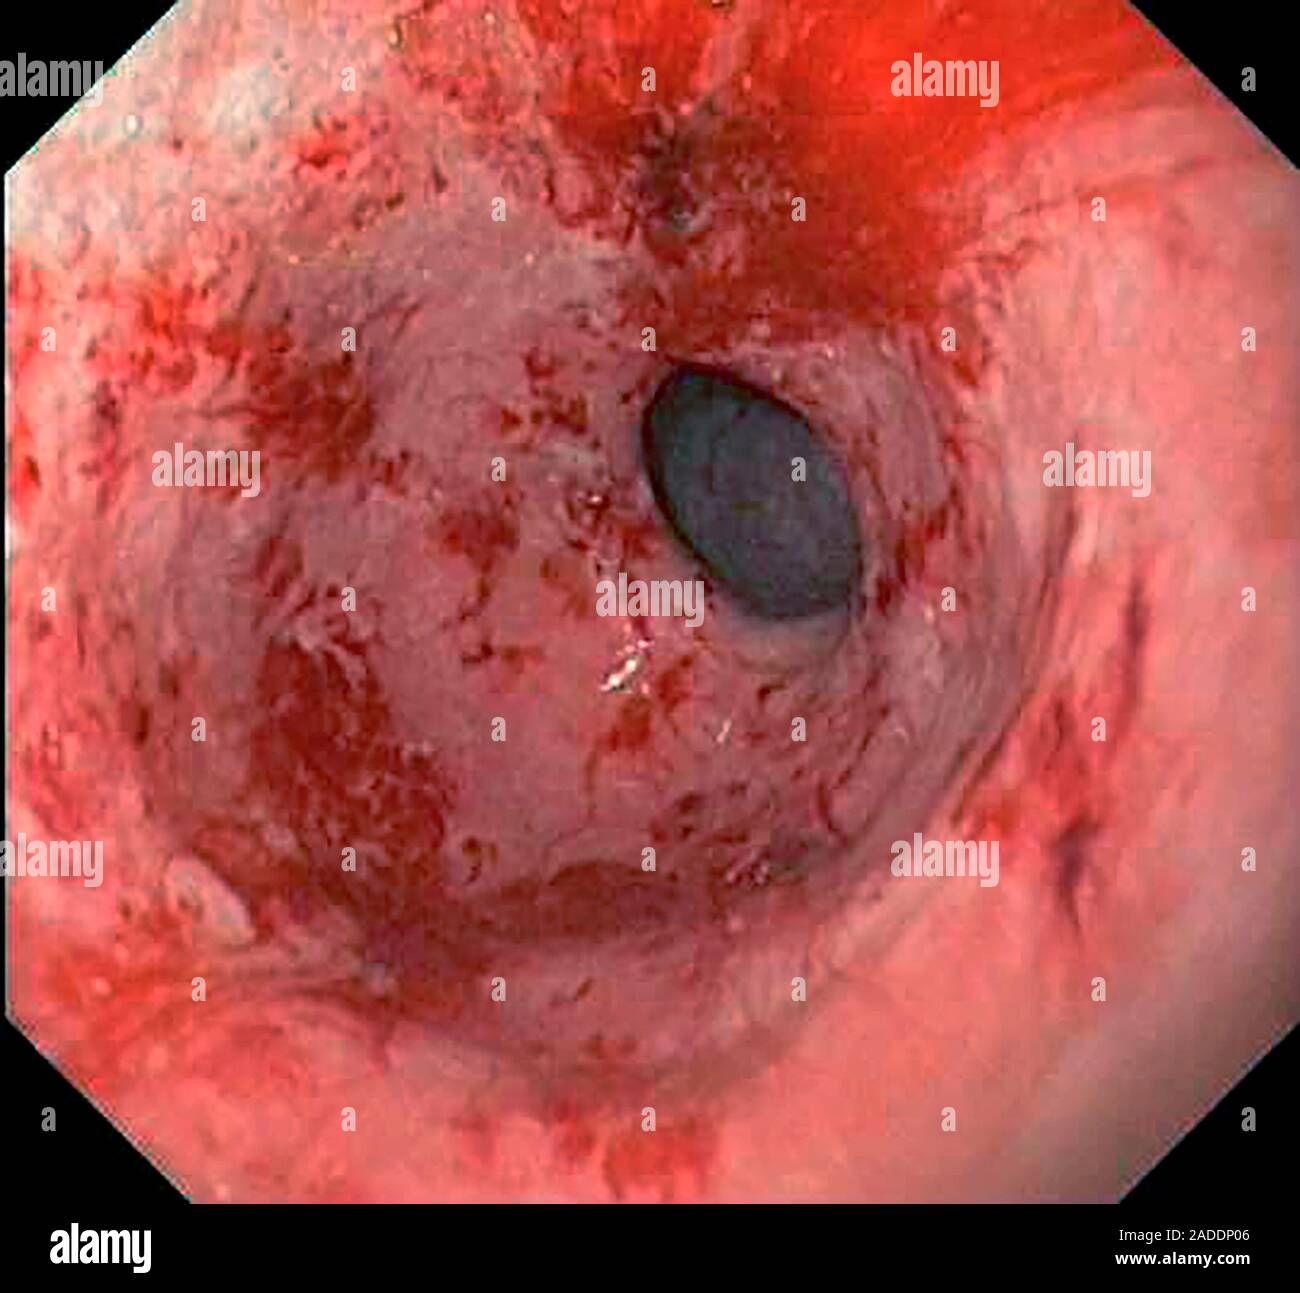

Gastric antral vascular ectasia. Endoscope view of the antrum (final Vascular Ectasia Examples This review describes various vascular anomalies, in accordance with issva classification and terminology; Vascular lesions include acquired lesions (eg, pyogenic granuloma, nevus araneus) and those that are present at birth or arise shortly after birth. Telangiectasias are small dilated blood vessels found anywhere on the body, but commonly seen on the face around the nose, cheeks, and chin. (1) zonated/lobular. Vascular Ectasia Examples.